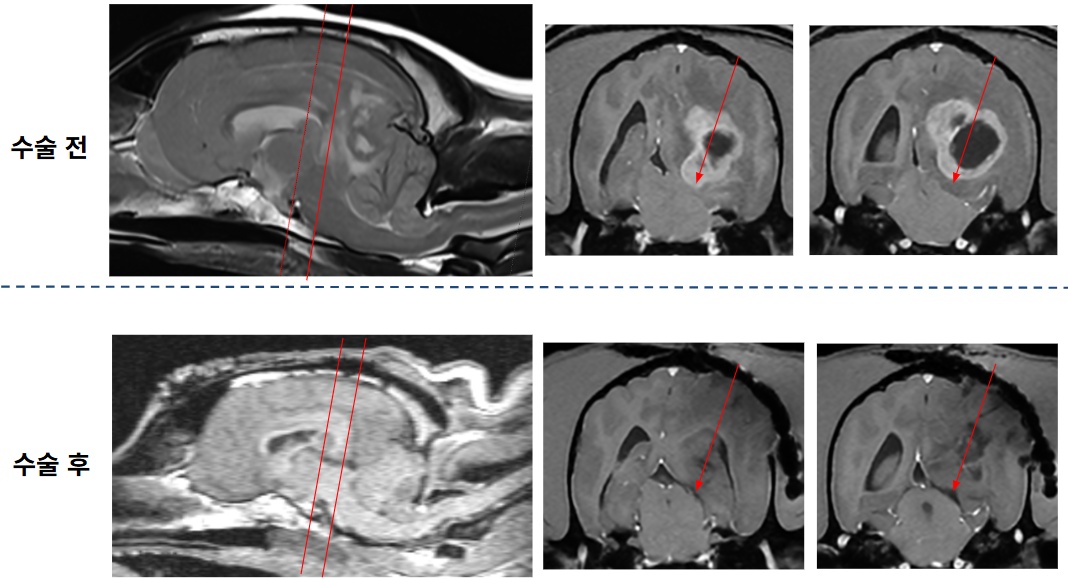

12살 암컷 웰시코기 환자는 기립불능과 의식 저하를 보이며 내원했다. 초기 신경학적 검사에서 전반적인 신경 반응 저하가 확인됐으며, 특히 연하반사 부재가 뚜렷해 중증의 뇌신경계 이상이 의심됐다. 뇌 MRI 촬영 결과, 좌측 대뇌반구 심부에 위치한 종괴성 병변이 확인됐으며, 영상학적 특성상 수막종(meningioma)의 가능성이 높게 판단됐다.

이외에도 광범위한 뇌부종, 대뇌낫의 우측 변위(midline shift), 소뇌 압박 및 탈출 소견이 함께 관찰됐다. 뇌간 압박까지 동반한 매우 위중한 상태였다.

수술 직후 촬영한 MRI에서 뇌간 압박의 완전한 소실이 확인됐으며, MRI 촬영 중 자발호흡도 회복됐다. 약 6시간 후 환자의 상태가 안정되어 발관도 가능해졌다.

환자는 수술 다음 날 신경학적 평가에서 좌측 위협 반사(menace response) 외 모든 기능이 정상화됐다. 또한, 스스로 식욕을 보이고 기립 및 보행까지 가능한 수준으로 회복했다.

술후 2일째, 뇌파검사에서 수술 전에는 보이지 않던 정상 뇌파 패턴이 재출현했다.